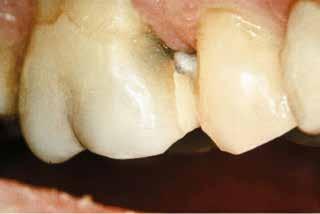

Restaureringer med KUN ÉN FARVE

Transcend universal komposit tilbyder et uovertruffent farvematch med kun én

Universal Body farve, takket være den patenterede Resin Particle Match™ teknologi, som eliminerer behovet for et blokeringsmateriale.

Hvis du foretrækker en lagvis teknik, fås Transcend komposit også i

En dybtliggende amalgam-misfarvning udgør en af de mest vanskelige udfordringer ved udskiftning af restaureringer. Transcend Universal Body farven blev anvendt til at erstatte amalgamen, uden brug af blokeringsmateriale. Bemærk, hvor fremragende farven blender ind i den bevarede crista obliqua.

eu.ultradent.blog

Scan QR koden for at se mere om Transcend komposit eller besøg ultradent.eu/transcend

Før Efter